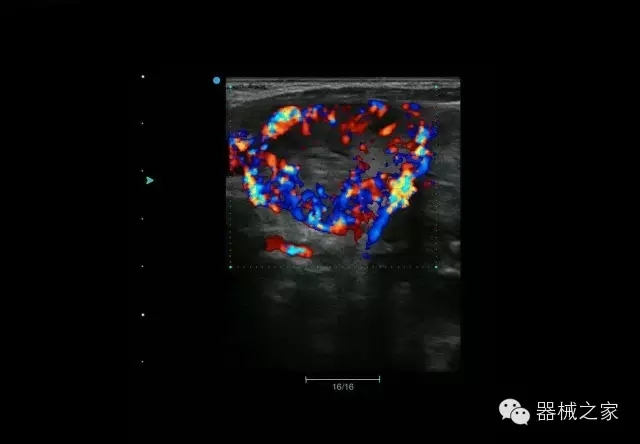

頸動(dòng)脈頻譜